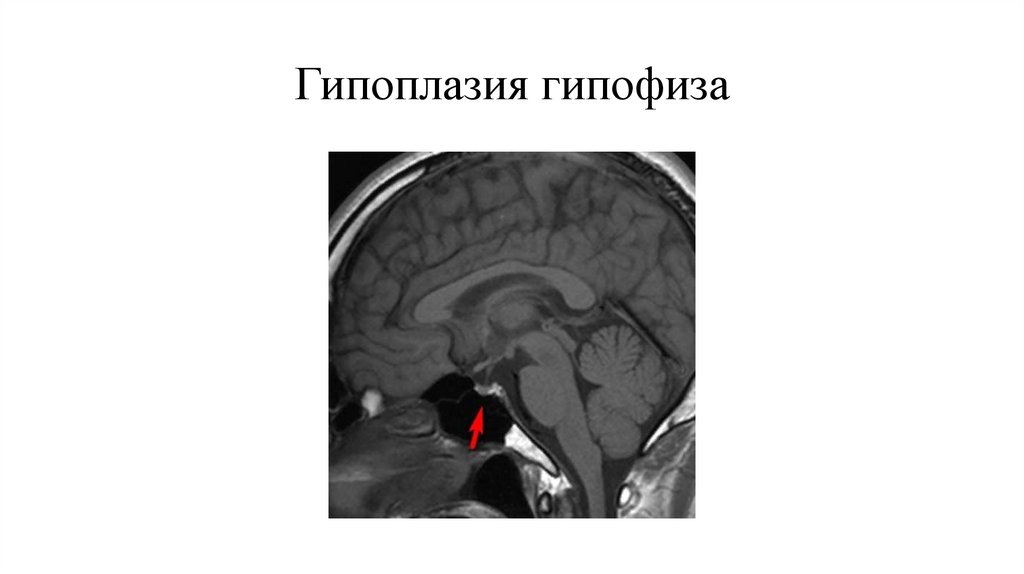

Гипоплазия гипофиза

Гипоплазия гипофиза недоразвитие гипофиза, обычно наблюдается при анэнцефалии.